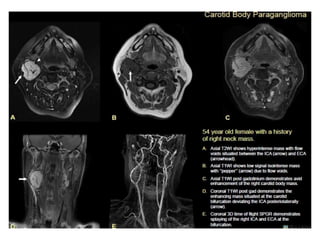

O documento fornece informações sobre como realizar exames de ressonância magnética do pescoço e angiorressonância magnética das carótidas, incluindo parâmetros, programação, anatomia, exames estruturais e funcionais, dicas e protocolos.